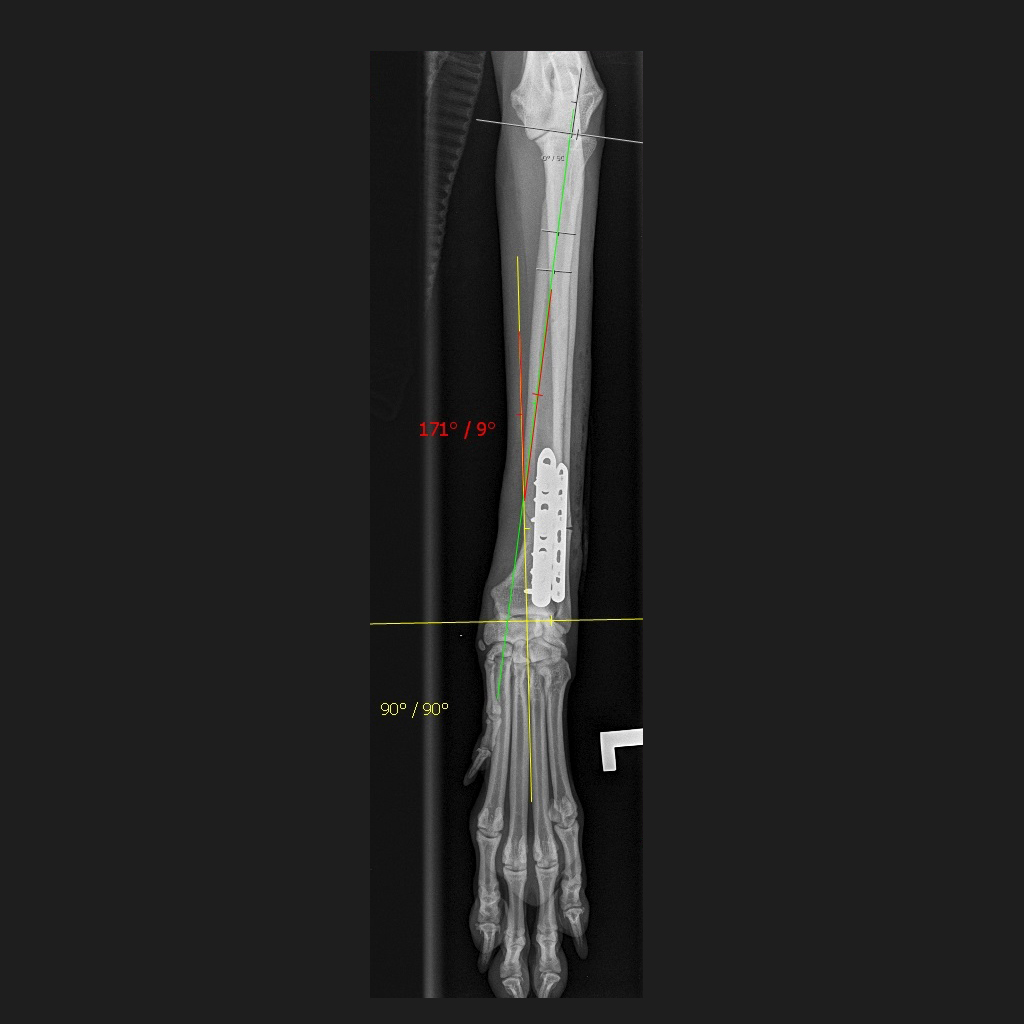

If further investigations are needed, then these typically will take the form of radiographs or CT assessments. These investigations are crucial to fully assess the deformity and to help determine if treatment is required.

In young animals with growth problems, surgery may be aimed at the active growth areas, seeking to adjust the remaining growth of the bone. In older patients, the bone may need to be realigned, and this will be guided by information from the radiographs or CT assessment.

Complicated cases with 3D deformities of the bone may benefit from CT guided surgery using specially designed templates to fit the bone precisely.